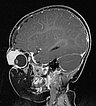

T1-weighted sagittal MRI after contrast administration. The bulb of the left eye is displaced caudally and dorsally by the expansion of the mass intraorbitally and the eyeball is depressed.